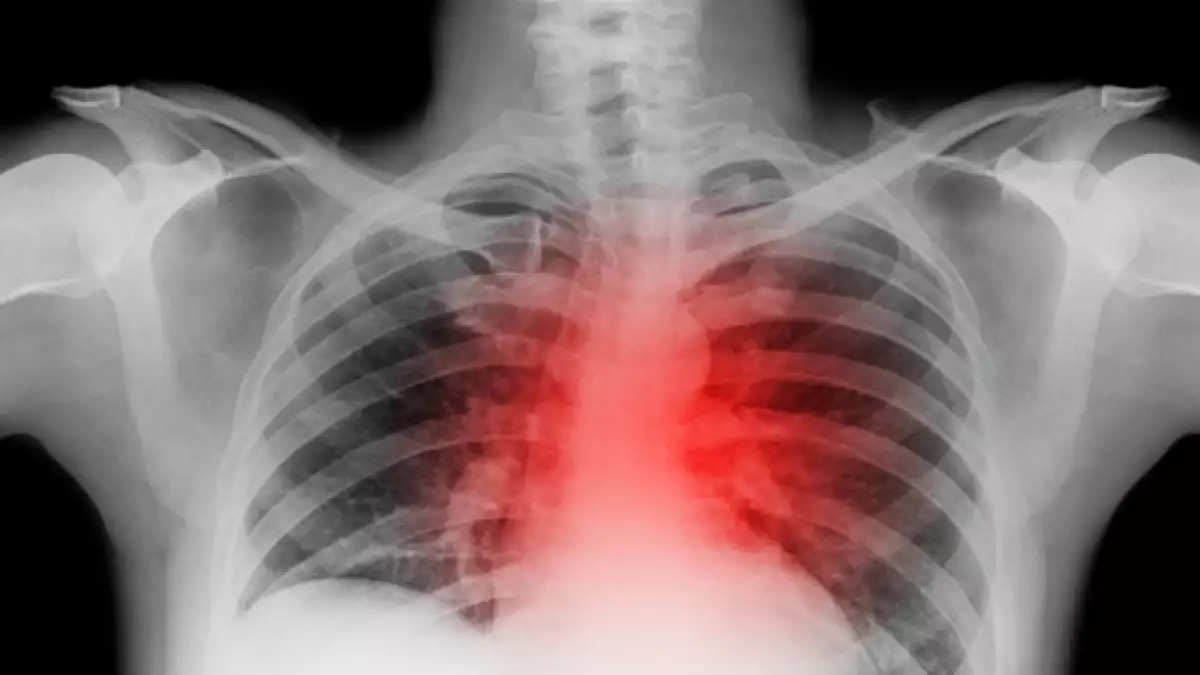

(CNN)— Lo que haces los primeros minutos durante un ataque cardiaco puede determinar toda una vida.

Desafortunadamente, no muchas personas conocen los síntomas a los que hay que estar atento o cuáles son las medidas que salvarán su vida. La siguiente información puede ayudar a que tú o algún conocido sobrevivan a un ataque cardiaco.